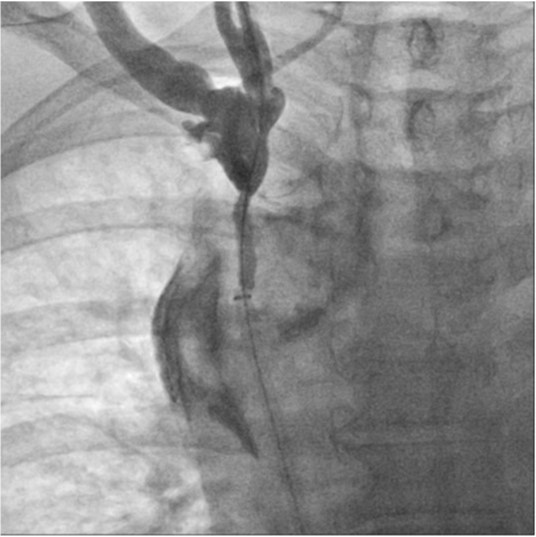

Fig. 3.

Fig 3. Fluoroscopic image shows guidewire passed across the obstructed segment. But the tip of the guidewire is positioned behind the right brachiocephalic vein (arrow).

초음파 유도 하에 우측 팔의 동정맥루 graft를 천자한 후 정맥조영술을 시행하여 우측 상완두정맥의 폐색을 확인함(Fig. 1). 5Fr Cobra 카테터(Cook, Bloomington, IN, USA)와 친수성 0.035 inch 유도철사(Terumo, Tokyo, Japan)로 폐색부위의 통과를 시도하였으나 실패함. 우측 대퇴정맥을 천자하고9Fr 65cm sheath (Arrow, Deutschland, Erding, Germany)를 상대정맥까지 진입시킨 후 5Fr Davis 카테터를 통해 약 2cm 길이의 상완두정맥 폐색 부위를 확인함(Fig. 2). Davis 카테터와유도철사로 상대정맥에서 우측 상완두정맥으로 통과를 시도함. 유도철사의 soft tip 부분으로 시도하였을 때 통과가 되지 않아서 반대쪽 hard tip 부분으로도 통과를 시도 하였으나 실패함(Fig.3). 유도 철사의 soft tip 과 hard tip 양쪽 모두 사용 하여 통과를 시도하였으나 막힌 부위의 위쪽 부분은 앞쪽(anterior side of the body) 을 향하고 있고 아래쪽 부분은 뒤쪽(posterior side of the body)를 향하고 있어서 천자 방향을 맞추기 어려웠음(Fig. 3). 우측 내경정맥을 천자하고 5Fr sheath를 삽입함. Sheath를 통해서 5FrKumpe 카테터와 0.035 inch 유도철사로 위에서 아래 방향으로 폐색부위 통과를 시도함. Hard tip으로 시술 도중 폐색혈관 주위로 유도 철사가 천자되어서 조영제의 누출이 있었으나 천자부위 주에 국한되어 있었고 임상적으로 문제 있는 혈류역학적 변화는 오지 않았음. Kumpe 카테터와 유도철사로는 천자 방향을 맞추기가 어려워서TIPS set (Cook, Bjaeverskov, Denmark)를 사용하기로 함. 천자된내 경정맥에 10Fr introducer sheath를 삽입하고 20G Colapinto needle을 폐색부위까지 진입시킴. 양쪽에서 정맥 조영술을 시행하여 폐색된 부위의 위치와 길이를 여러 각도에서 정확히 파악한 후, 폐색 부위를 천자함(Fig. 4). 천자 후 Colapinto needle을 통해 유도철사를 상대정맥에 진입시킴. 대퇴동맥을 통하여 삽입된 snare 카테터(ev3, Plymouth, MA, USA)를 이용하여 대퇴정맥 밖으로 유도철사를 빼냄(through and through technique)(Fig 5). 유도 철사만 통과된 상태에서 천자부 주위에 여러번의 천자로 인한 조영제 누출이 있었으나 주출된 조영제의 양이 적었으며 천자부 주위에 국한되어 있었음. Tractogram시행시 조영제의 누출은 보이지 않아서 유도 철사 주위에 국한 되어 있어서 풍선확장술을 시행 하기로 함(Fig. 6).대퇴 정맥을 통해 유도철사를 0.035 inch Amplatz wire(Cook, Bjaeverskov, Denmark)로 교체하여 내경정맥까지 진입시킨 후 풍선카테터 (Bard, NJ, US)를 삽입함.천자된 통로를 따라 직경 6 mm에서부터 16 mm까지의 풍선카테터로 차례대로 풍선확장술을 시행함(Fig. 7). 시술 후 정맥조영술에서 폐색부위는 개통되어 원활한 혈류를 보였음(Fig. 8). 시술 후에 오른쪽 팔의 종창은 호전됨.